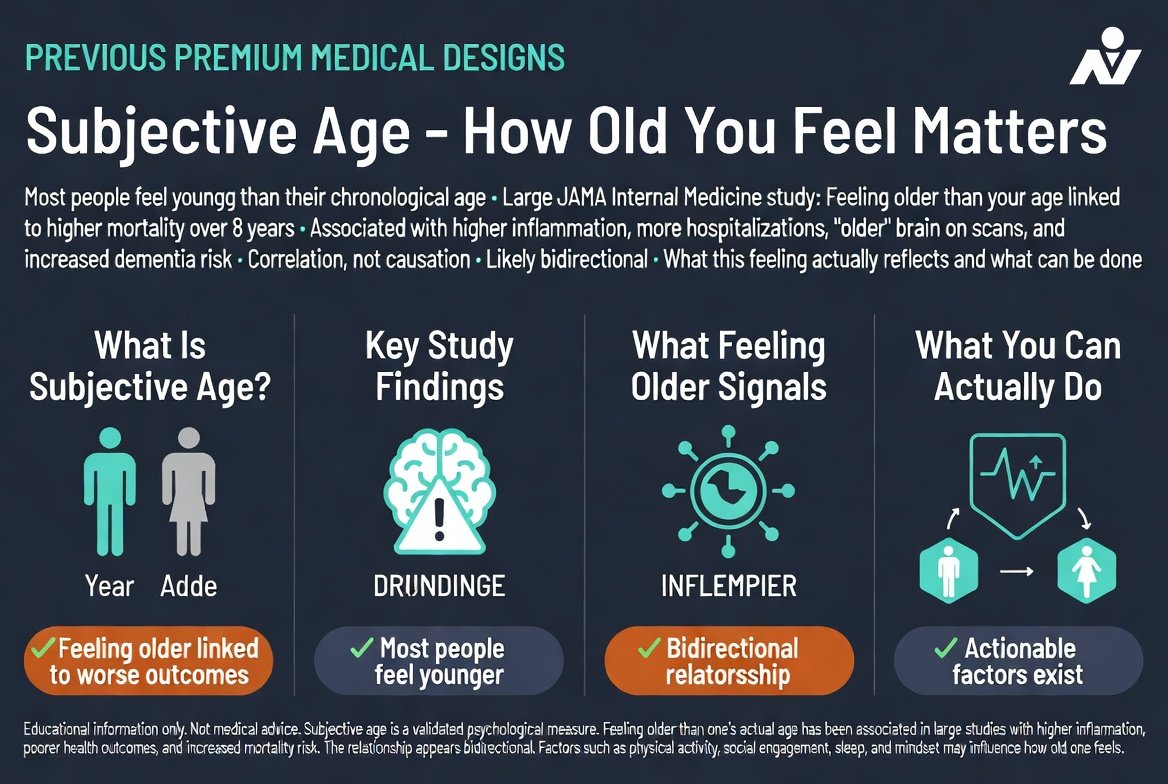

גיל סובייקטיבי: בן כמה אתה מרגיש ואריכות חיים

אם ישאלו אתכם בן כמה אתם מרגישים, רוב הסיכויים שתנקבו במספר נמוך מהגיל בתעודת הזהות. זה לא רק נחמד לאוזן: 'גיל סובייקטיבי', התחושה הפנימית של בני כמה ...

אם ישאלו אתכם בן כמה אתם מרגישים, רוב הסיכויים שתנקבו במספר נמוך מהגיל בתעודת הזהות. זה לא רק נחמד לאוזן: 'גיל סובייקטיבי', התחושה הפנימית של בני כמה ...